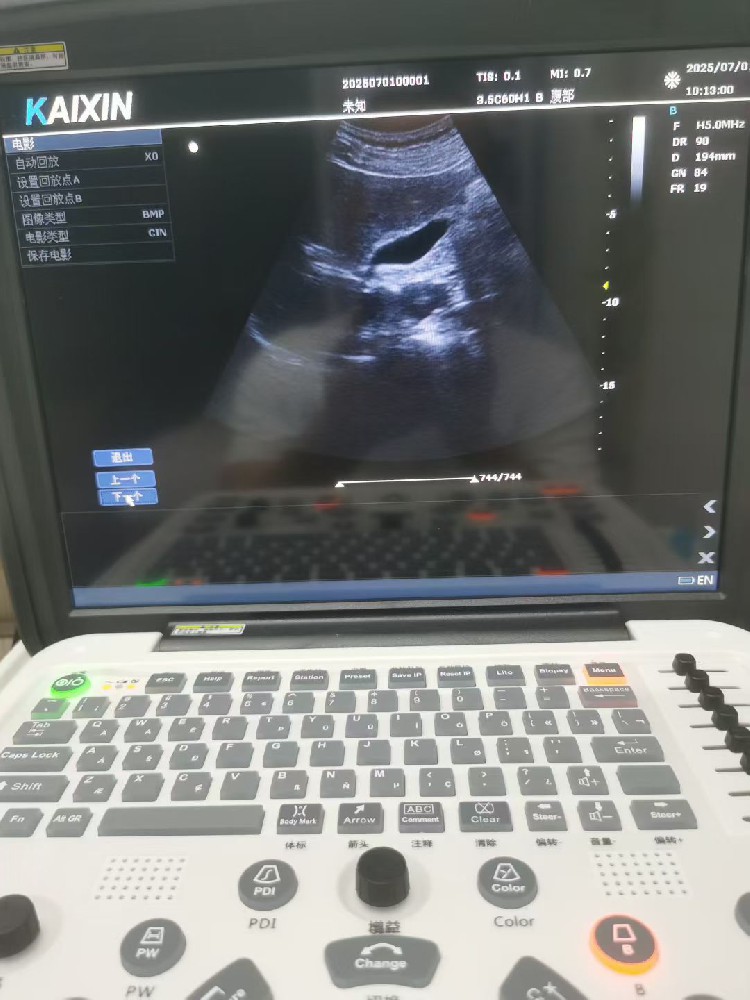

一、产品预期用途适用于腹部、产科、妇科、心脏、血管、小器官、泌尿科、矫形外科(儿科/肌骨)检查。二、产品特点• 23.8" 彩色液晶显示器• 具有自动识别技术,···...